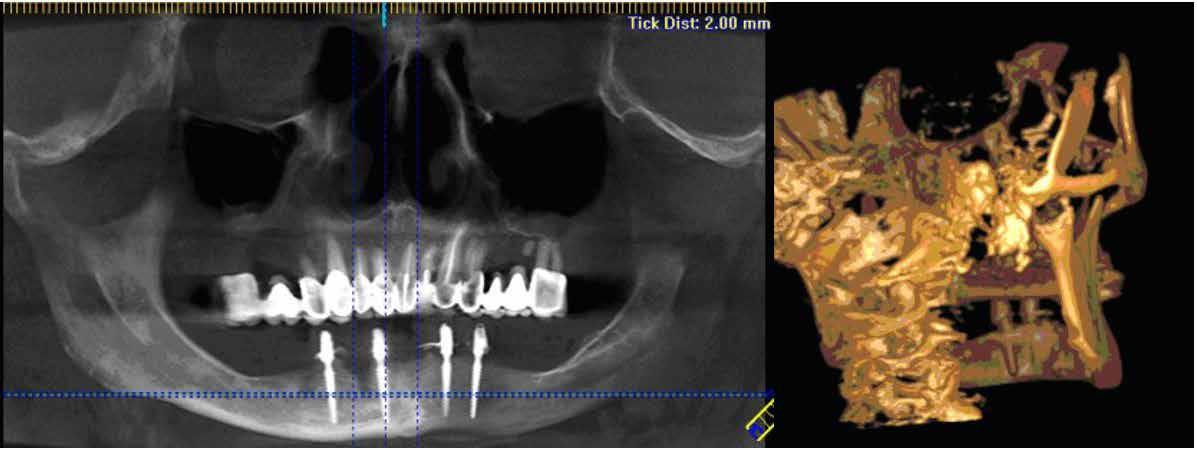

Az európai uniós rendeletekkel való harmonizáció keretében új szakvizsgák, feltételek, követelményrendszer alakult ki a hazai sztomatológiában. Megjelent az új orális implantológia szakvizsga, és egészen új szintre került a többi fogászati szakorvosi vizsga követelményrendszere is. Az új szakvizsgákhoz tartozó követelmények egyben a szakma új szabályainak is tekinthetőek, vagyis jelentős feladat elé állítják a rendelőket. A fejlődést a páciensek is nyomon követhetik az interneten keresztül, és ezzel új, és a réginél sokkal magasabb igényszintű fogászatot, implantológiát elvárásként fogalmazhatják meg. Ha ezt az új színvonalat, a fejlődést kevéssé követő fogorvosi rendelővel szemben várják el, akkor az ott végzett kezelések után kialakulhat a „konfliktus szituáció.” (1–3. képek)

Az implantológiában inkább a szájsebészeti jellegű témák voltak hangsúlyosak, a manuális eljárások dominanciája volt jellemző. Ma inkább a különleges csontpótlásokról, az előre megtervezett fogpótlásból (backwards planning = visszafelé tervezés) kiindult sebészeti tervezésről esik sok szó, ez vált követelménnyé. A digitális eljárások fölénybe kerültek a manuálisokkal szemben. A régi technológiák folyamatosan kikopnak a gyakorlatból. És itt is kérdés: Mi az, ami megfelel – még vagy már – a szakma szabályainak? Már csak emiatt is sok mindent újra kell gondolni (4–5. képek)